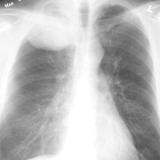

Lung Cancer

Nodules & Masses

Album: Nodules & Masses

Date: 01/25/2006

Size: 37 items

Views: 60060